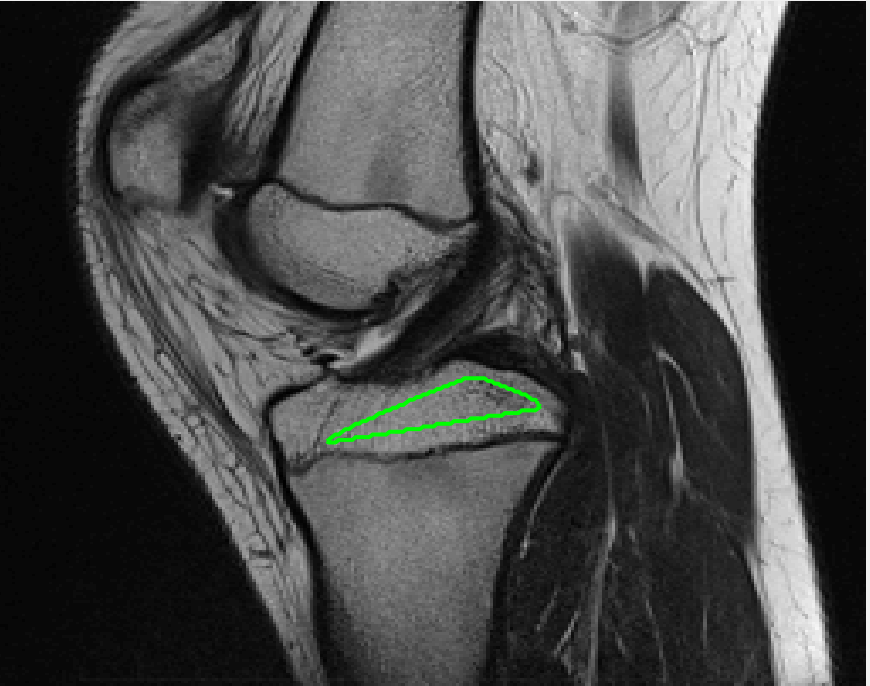

Four sets of test results are shown below. In Test 1 we compare models M1 – M6 to the proposed model M7 for two images which are hard to segment. The first is a CT scan from which we would like to segment the lower portion of the heart, the second is an MRI scan of a knee and we would like to segment the top of the Tibia. See Figure 9 for the test images and the marker sets used in the experiments. In Test 2 we will review the sensitivity of the proposed model to the main parameters. In Test 3 we will give several results achieved by the model using marker and anti-marker sets. In Test 4 we show the initialisation independence and marker independence of the Geodesic Model on real images.

Refer to captionRefer to captionRefer to captionRefer to caption

(i)                                 (ii)                                 (iii)                                 (iv)

Figure 9: Test 1 setting: (i) Image 1;  (ii) Image 1 with marker and anti-marker set shown in green and pink respectively;  (iii) Test Image 2; (iv) Image 2 with marker set shown.